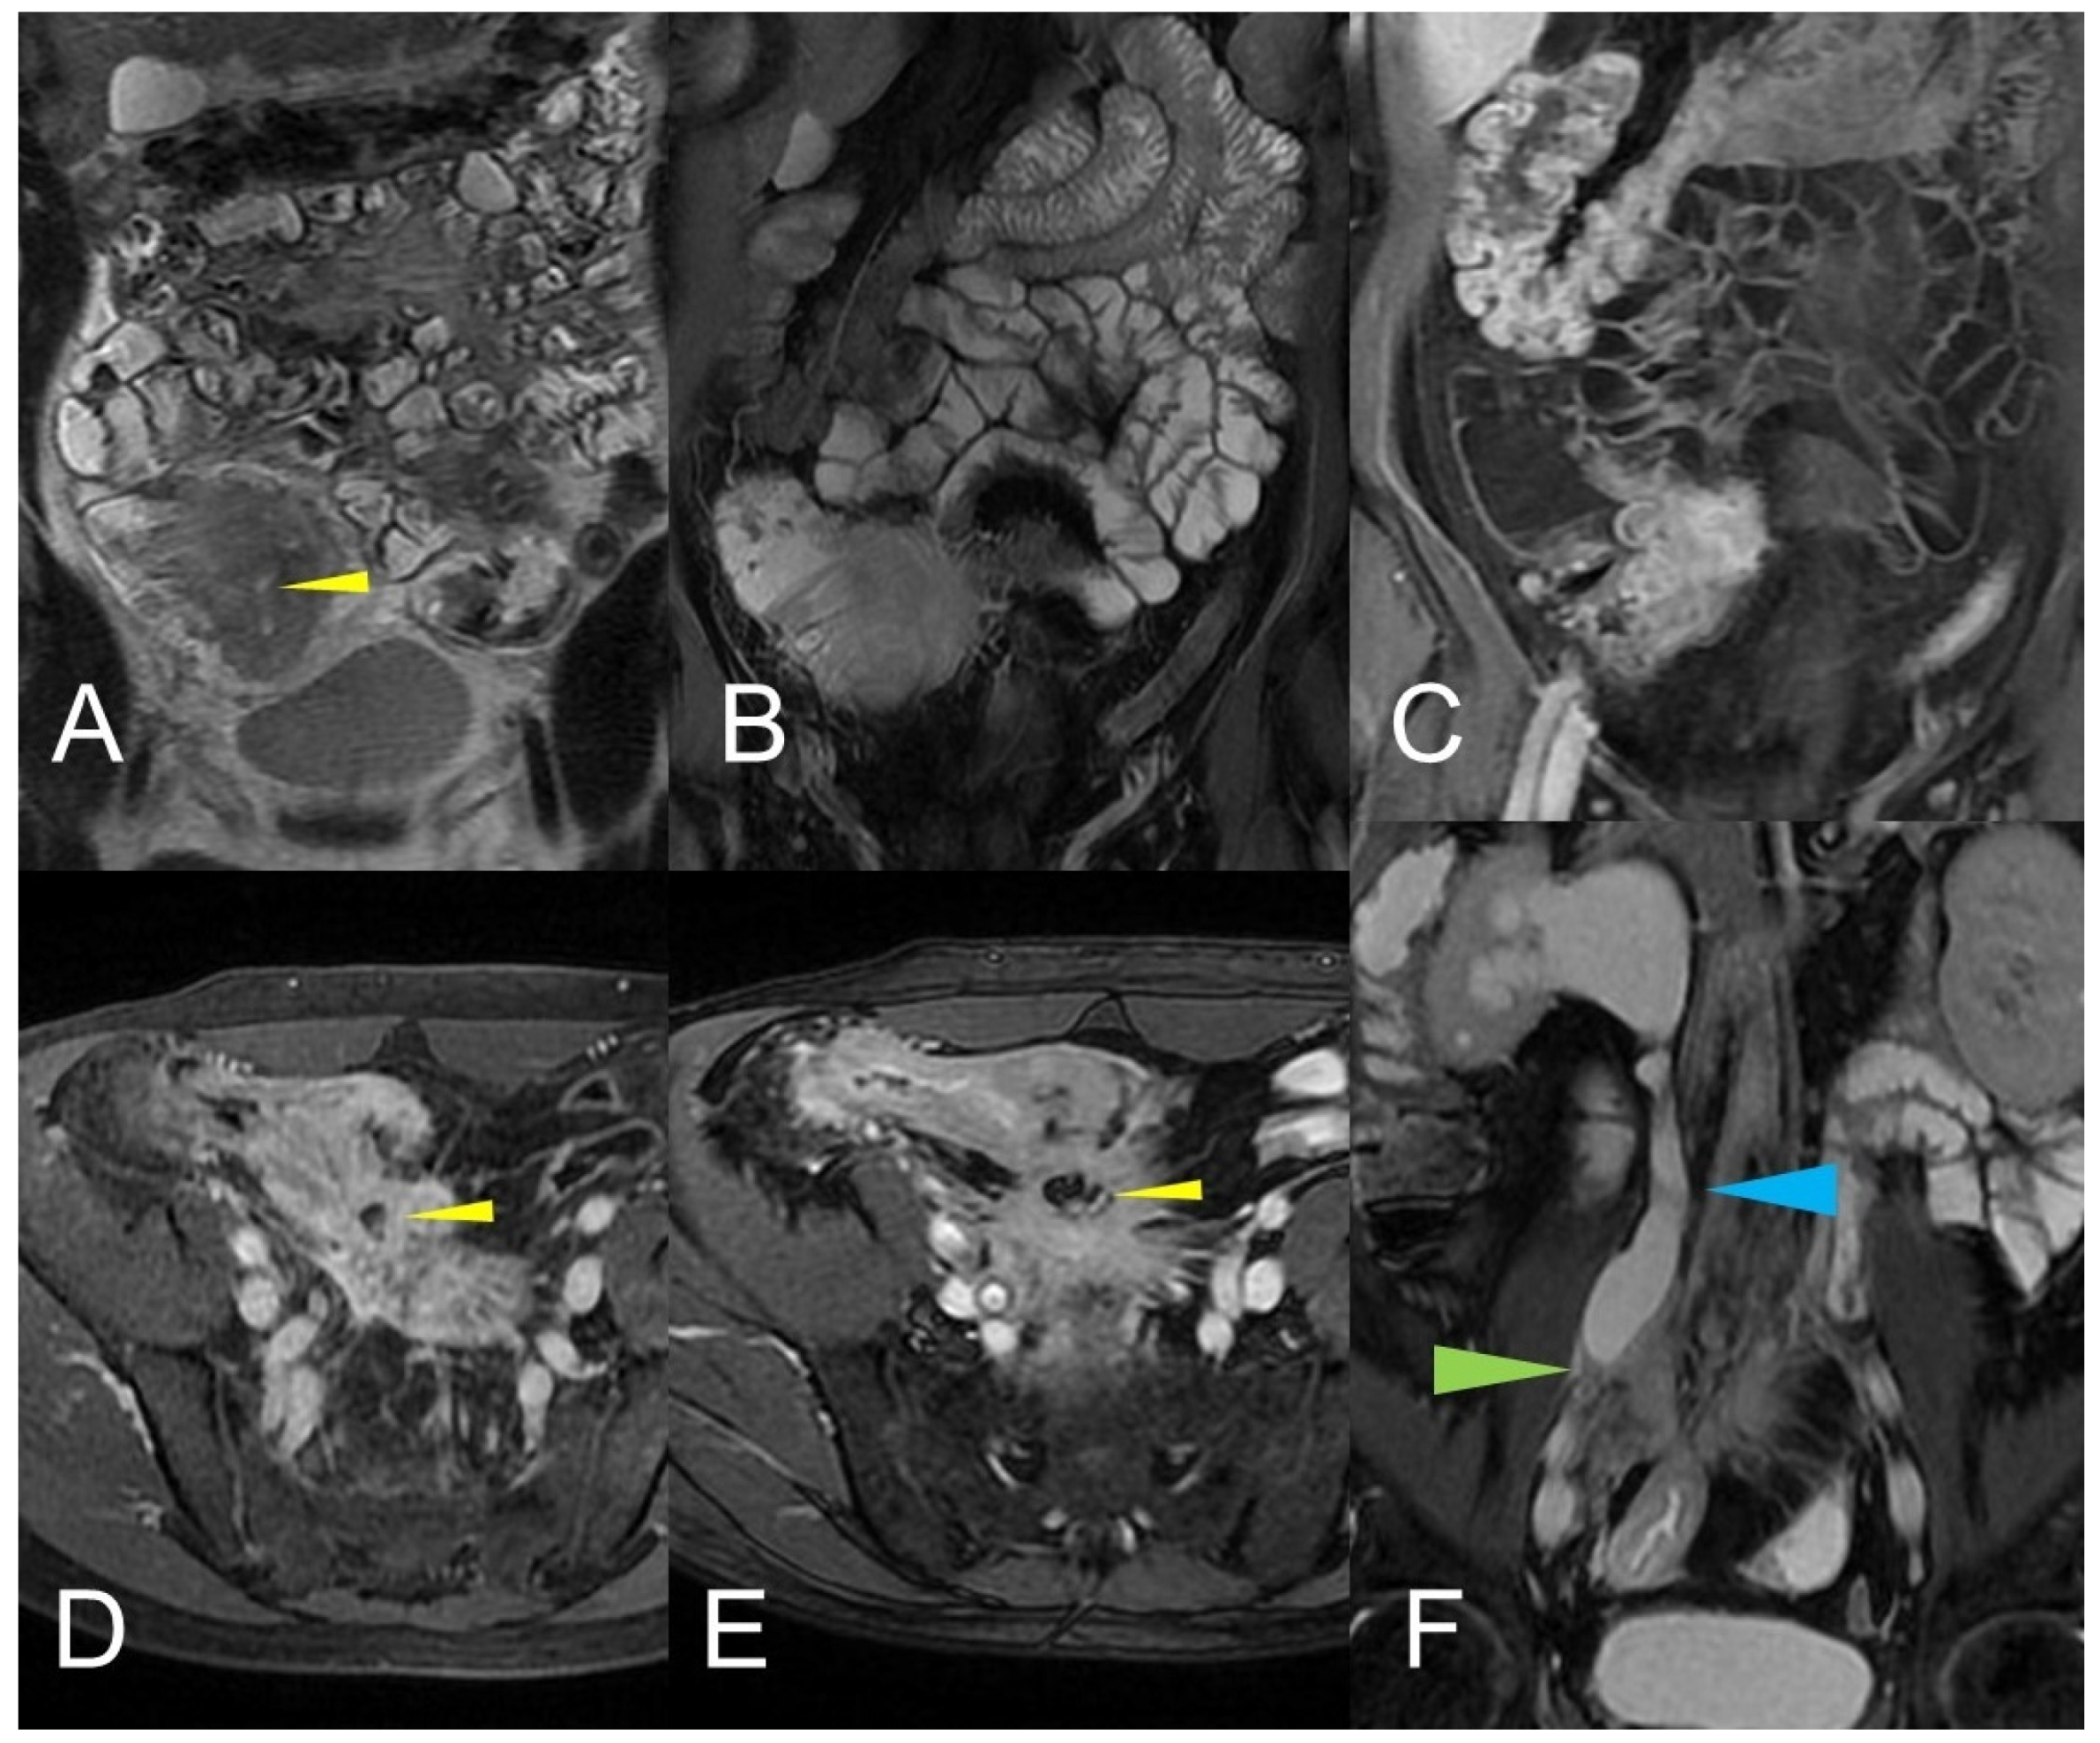

Figure 14.

Large climbing inflammatory conglomerate. A small abscess is evident in the center of the inflammatory conglomerate (yellow arrowheads in (A,D,E)). It shows marked enhancement (yellow arrowhead in (C)) and determines conspicuous retracting effects both on the mesentery (spiculate aspect in (D,E)), in which it develops, and on the adjacent loops. In this patient, the right distal pelvic ureter is also narrowed, (green arrowhead in (F)) with hydronephrosis (blue arrowhead in (F)). (A): coronal T2-weighted MRE image; (B,F): coronal fast imaging employing steady-state acquisition (FIESTA) image; (C): coronal contrast-enhanced fat-suppressed T1-weighted image; (D,E): axial contrast-enhanced fat-suppressed T1-weighted image.